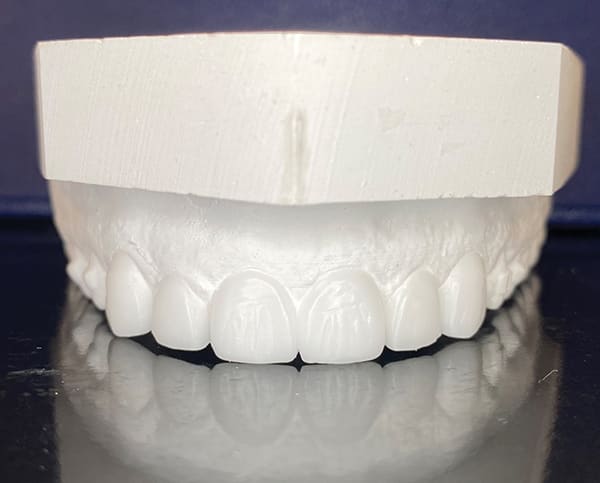

A 46-year-old female patient presented with the chief complaint of disliking the shape, color, and spacing of her front teeth. After conducting online research, the patient was adamant she did not want veneers or traditional bonding but instead preferred Bioclear® composite restorations (Bioclear, bioclearmatrix.com) on her maxillary and mandibular anterior teeth to preserve tooth structure. An intraoral scan using the iTero Element® 2 intraoral scanner (Align Technology, Inc, itero.com) and photographs were taken. It was discussed with the patient that prior to final restorations Invisalign® clear aligner therapy (Align Technology, Inc, invisalign.com) was needed to close all mandibular spacing (eliminating the need for restorations) and partially close the maxillary spacing (improving the height-to-width ratios of the final maxillary restorations). The patient completed Invisalign treatment in 15 weeks and then whitened with Opalescence™ PF 10% whitening gel (Ultradent, ultradent.com). An intraoral scan with the iTero Element 2 scanner was taken for a pre-prosthetic lab wax-up of teeth Nos. 6 through 11. These teeth were restored with full esthetic composite veneers using the Bioclear heated composite injection overmolding technique with Filtek™ Supreme Ultra Universal Restorative White Body paste and flowable (3M Oral Care, 3m.com). No tooth structure was resected. The patient was immediately scanned for Vivera® retainers. She was thrilled with her smile transformation.

Direct composite restorations with the Bioclear method

are minimally invasive, additive, and esthetically natural looking.